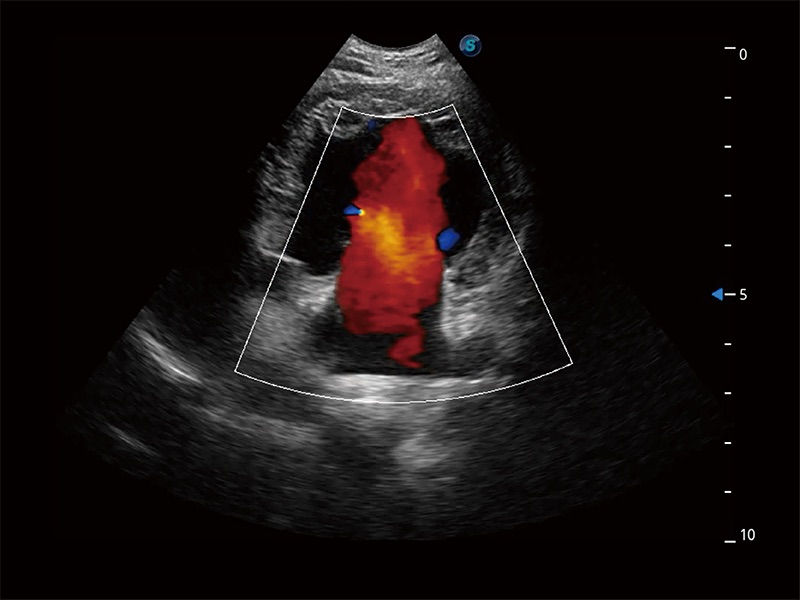

(犬)胎儿主动脉弓立体血流